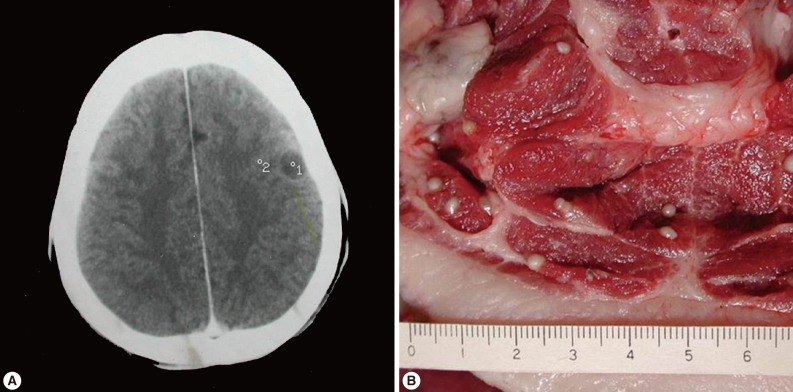

Human Neurocysticercosis Case and an Endemic Focus of Taenia solium in Lao PDR

The Korean Journal of Parasitology 2013;51(5):599-602.